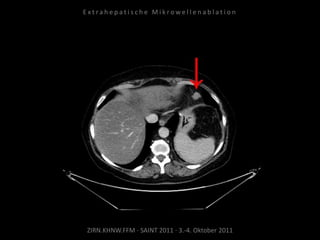

Bildgebung vor MWA:

CT 14.03.2011

Situation:

Nur 1 Metastase, diese ist jedoch

progredient. Kritische Lage in

Herznähe.

Ablation am 24.03.2010:

2 Nadelpositionen.

Kontrolle:

MRT 05.04.2010

Kein weiteres Wachstum.

Verlaufskontrolle:

CT 24.06.2010

Behandelte Metastase nicht progredient.

Neu ist ein subkapsuläres Biliom DD

Serom DD Hämatom der Leber.